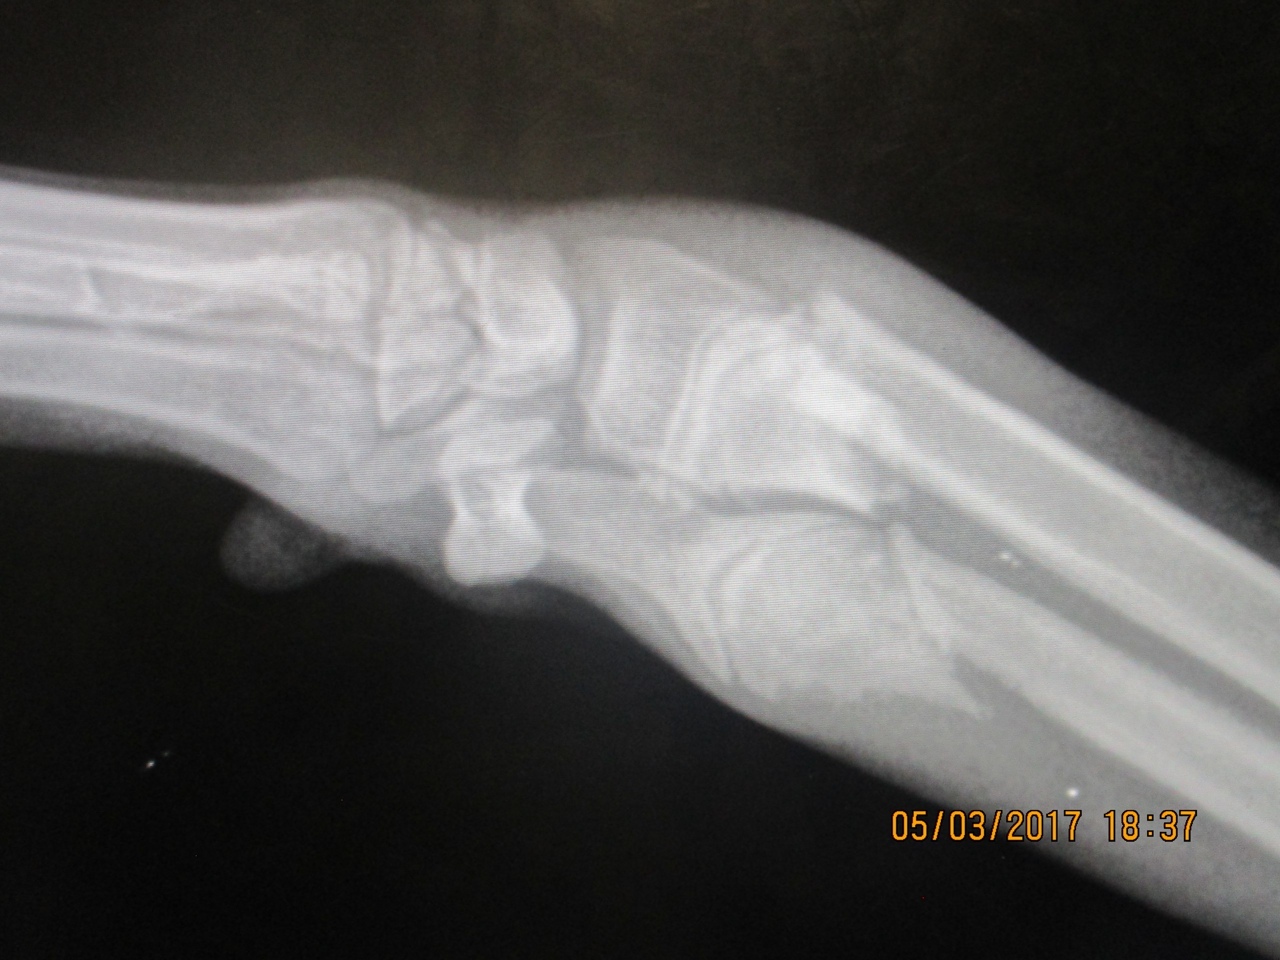

Да, для нас Зена настоящая красавица. Но мы поняли, что нет у нее будущего. Так и проведет свою жизнь бедная девочка в стенах приюта, каждый раз провожая непонимающим взглядом очередных счастливчиков. А все из-за лапы, которую в детстве повредили и уже не стали восстанавливать.

Зена в МП г.Перми со щенка. Лапы, которая не мешает Зене бегать, ходить, сидеть, лежать. Перелом был еще в щенятнике очень близок к ростовым точкам, на момент обнаружения уже сросшийся, а пока лапа не выросла до взрослого состояния ломать и делать ровной было нельзя, позже уже незачем. Зене она не мешает, неужели вам она помешает?